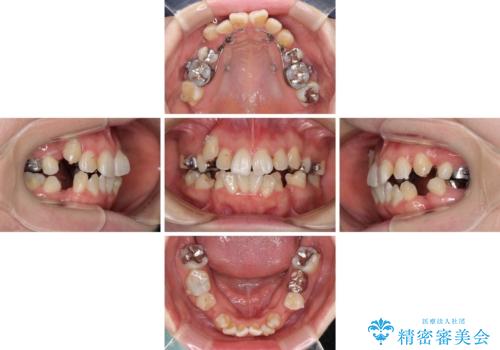

- 八重歯やデコボコを気にして来院された患者様です。

お住まいから船での通院となることから、補助装置を使用しながらインビザラインにて上下左右第一小臼歯4本を抜歯した矯正治療を行うこととしました。

ところが、インビザラインでの自己管理が煩わしいと感じてしまい、途中で矯正治療を投げ出すことになってしまいました。

相談の上、表側の目立ちにくいワイヤー装置により矯正治療を継続していくこととしました。

マウスピース(インビザライン)はほとんど使用することができませんでしたが、補助装置により上顎の八重歯は改善しておいたので、ワイヤー装置ではスムーズに治療を終えることができました。